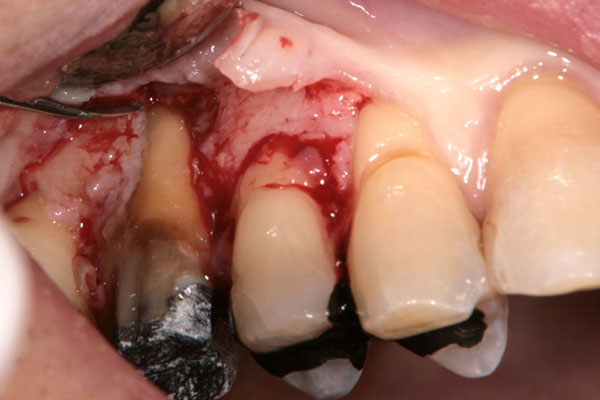

歯周病が進行すると、治療器具が届かないほど歯周ポケットが深くなることがあります。こうなると、通常の方法では歯周ポケットの中の歯石を取り除くことはできません。

このような場合は、外科的に歯肉を切り開いて歯石などを取り除く「歯周外科治療」を行います。

「FOP法」は、歯肉を切り開いて奥深くの歯石を取り除く術式です。直接目で見ながら歯石を取り除けるので、ほとんど取り残しがありません。